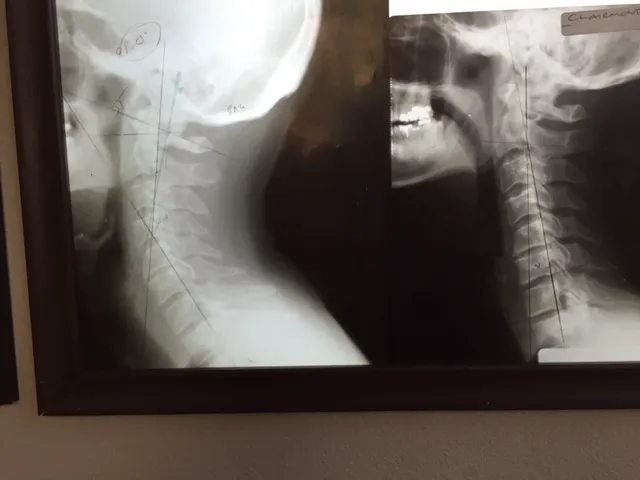

Chiropractic care, at its core, focuses on the diagnosis, treatment, and prevention of mechanical disorders of the musculoskeletal system, particularly the spine, and their impact on nervous system function and overall health. What distinguishes Gonstead Clinics and Dr. Eric Pastrmac is their adherence to the precise and thorough Gonstead System of Chiropractic. This methodical approach involves detailed analysis, including full spine X-rays, static and motion palpation, visualization, and nervoscope readings, to pinpoint the exact location of subluxations (misalignments) in the spine. This precision allows for highly specific and effective adjustments, leading to remarkable patient outcomes. Dr. Pastrmac’s dedication to this meticulous method, combined with his evident skill, has earned him a reputation that extends far beyond Irvine, drawing patients from as far as Los Angeles and beyond.

- Gonstead Spinal Adjustments: The core service, involving detailed analysis using full spine X-rays, nervoscope, palpation, and visualization to identify specific vertebral subluxations. Adjustments are then performed with precision to correct these misalignments, optimizing nervous system function.

- Restoration of Spinal Curvature: Specialized techniques to help restore the natural and healthy curvature of the spine, particularly in the neck (cervical lordosis), which can be crucial for long-term relief from tension and pain.

- Specific Vertebral Correction: Focus on correcting specific misalignments, such as those in the C1, C2, and C4 vertebrae, as highlighted by patient testimonials, which can have profound effects on overall well-being and nerve function.

- Restoration of Neck Curvature and Specific Corrections: A notable highlight is Dr. Pastrmac's success in restoring the natural curvature of the neck and correcting specific, difficult-to-adjust vertebrae like C1, C2, and C4, leading to profound improvements in patient health.

Nov 16, 2021 · susan marozikDr. Pastrmac was able to relieve almost a decade of tension and stress in my neck and back. After my first visit I already noticed a huge difference. He fixed my C1, C2, & C4, and over subsequent visits was also able to restore the curvature in my neck. Years of tension and soreness in my shoulders as well as the tightness in my chest are gone. His work is amazing; I was initially scared to get adjusted, but he put me at ease. I highly recommend him.